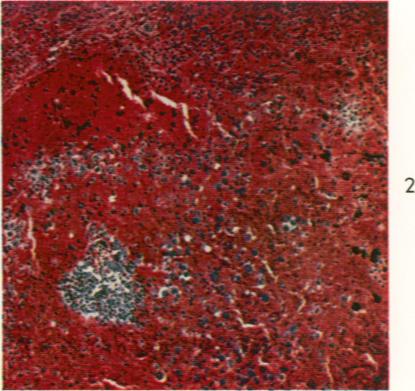

Human inhalation anthrax. A report of three fatal cases.

Am J Pathol. 1960 Apr;36(4):457-71.